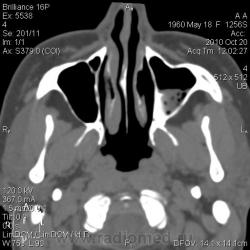

КТ. Нагноение кисты верхнечелюстной пазухи.

Женщина 30 лет, жалобы - головная боль, направлена для уточнения характера патологии ППН. Снимков пазух у меня нет.

Отграничено, ровный контур, гнойная (30 ед.Н) плотность

Да, надо признать, что уважаемая Людмила Григорьевна всегда старается объяснить, что не понятно коллегам. Но, я порассуждал с точки зрения «банальной эрудиции». Эта перегородка, в гайморовой полости, о чем свидетельствуют сканы, не полностью разделяет гайморову пазуху на две «изолированные полости», и сообщение между «разделениями» весьма не хилое есть, и если, предположить, что «то» сопли, то сопли, как всякая жидкая или полужидкая субстанция обязательно с учетом силы тяжести протекли вниз, чего не произошло, а, следовательно, процесс является, чем – то ограниченным, и имеющим определенную оболочку.

плотность. Есть серая шкала, от черного (воздух) до белого (кость). Остальное - оттенки серого. Я подобрала режим для демонстрации, чтоб наиболее выигрышно показать и пазуху, и ее содержимое. В данном случае больше вероятность за нагноение кисты: пузырьки газа, гнойная плотность патологического содержимого. Более жидкая субстанция растеклась бы, а полип имеет большую плотность (40-60 единиц). Было бы интересно проследить динамику, но пациентка категорически отказалась от пункции, так что вероятнее всего, что история на этом и закончится. А ППН можно и на животе делать с запрокидыванием головы назад - только для пациента не очень удобно, а при шейном остеохондрозе иногда и невозможно.

Без сомнений это острый процесс (гайморит), слизистая  клеток решетчатой кости тоже  неравномерно утолщена.